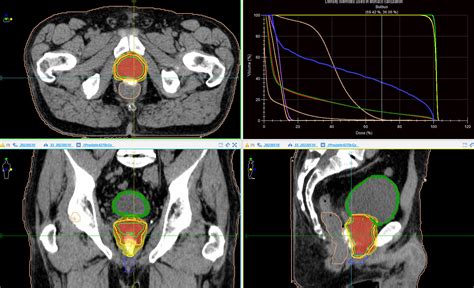

Prostate external beam radiation – Reno Cancer Center

904×488

renocancercenter.com